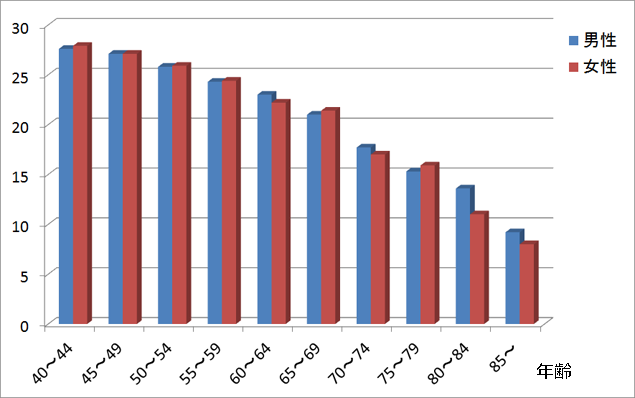

あなたの歯は何本残っていますか? (一人平均現在歯数)

平成23年度歯科疾患実態調査より作図、年齢別の平均残存歯数を表しています。